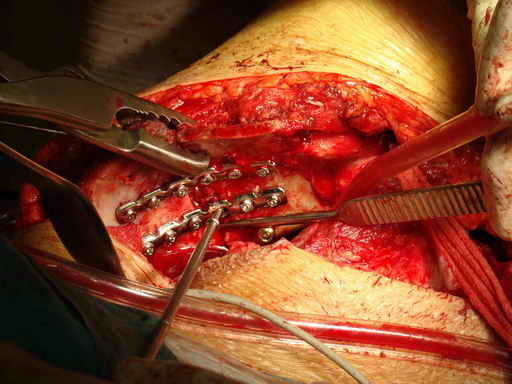

Остеосинтез подвздошной кости

Укладка тазовой пластины "matta"

Операционная. Оперирует д.м.н. проф. Казанцев А.Б.